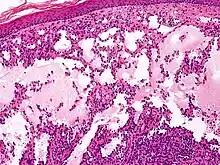

Cavernous lymphangioma, H&E stain. Irregular, dilated spaces are visible in dermis.

Lymphangiomas have traditionally been classified into three subtypes: capillary and cavernous lymphangiomas and cystic hygroma. This classification is based on their microscopic characteristics. A fourth subtype, the hemangiolymphangioma is also recognized.[9]

Composed of dilated lymphatic channels, cavernous lymphangiomas characteristically invade surrounding tissues.